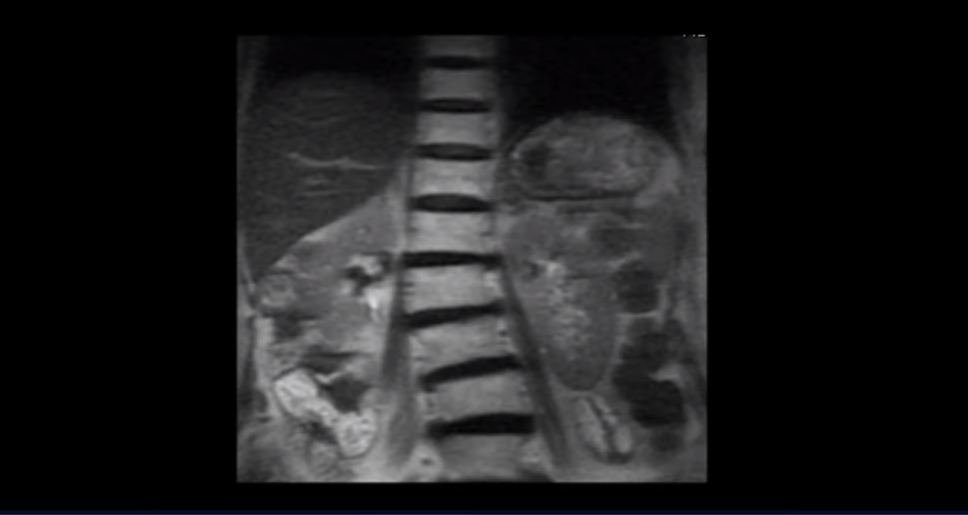

수술로 신경 눌림이 잘 풀려도 협착증 환자는 근육 문제 때문에 엉덩이와 다리가 얼마든지 아플 수 있습니다. 저희 모커리한방병원이 협착증 관련 설명 영상에서 수없이 반복해서 설명해 드리고 있는데 협착증 환자는 노화로 신경 구멍이 좁아져 있을 뿐만 아니라 근육이 많이 줄어들어 약해지고 근육에 문제가 생겨서 뭉치고 굳고 틀어진 상태입니다. 그걸 가장 쉽게 확인할 수 있는 게 70대 이상의 협착증 환자의 척추를 보면 모두 예외 없이 다 틀어지고 휘어있습니다.

이렇게 척추가 심하게 뒤틀려있다는 얘기는 근육에 심각한 문제가 있다는 얘기입니다. 협착증은 신경 구멍이 좁아진 것 외에도 반드시 이런 근육 문제가 동반되어야 협착증이 발병합니다. 그래서 모든 협착증 환자는 다 근육에 문제가 있다고 생각하시면 됩니다. 나이가 많은 고령일수록 근육의 문제는 더 심각하다고 보시면 됩니다.